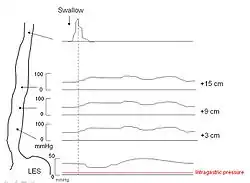

Esophageal manometry

Because of its sensitivity, manometry (esophageal motility study) is considered the key test for establishing the diagnosis. A catheter (thin tube) is inserted through the nose, and the patient is instructed to swallow several times. The probe measures muscle contractions in different parts of the esophagus during the act of swallowing. Manometry reveals failure of the LES to relax with swallowing and lack of functional peristalsis in the smooth muscle esophagus.[11]

Characteristic manometric findings are:

- Lower esophageal sphincter (LES) fails to relax upon wet swallow (<75% relaxation)

- Pressure of LES <26 mm Hg is normal, >100 is considered achalasia, > 200 is nutcracker achalasia.

- Aperistalsis in esophageal body

- Relative increase in intra-esophageal pressure as compared with intra-gastric pressure